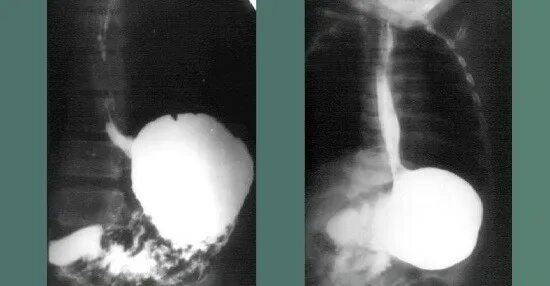

Рентгеноскопия пищевода и желудка с барием

Грыжа пищевода рентген с барием. скопия желудка рентген. параэзофагеальная грыжа рентген.

Грыжа пищевода рентген с барием. грыжа пищеводного отверстия на рентгене с барием.